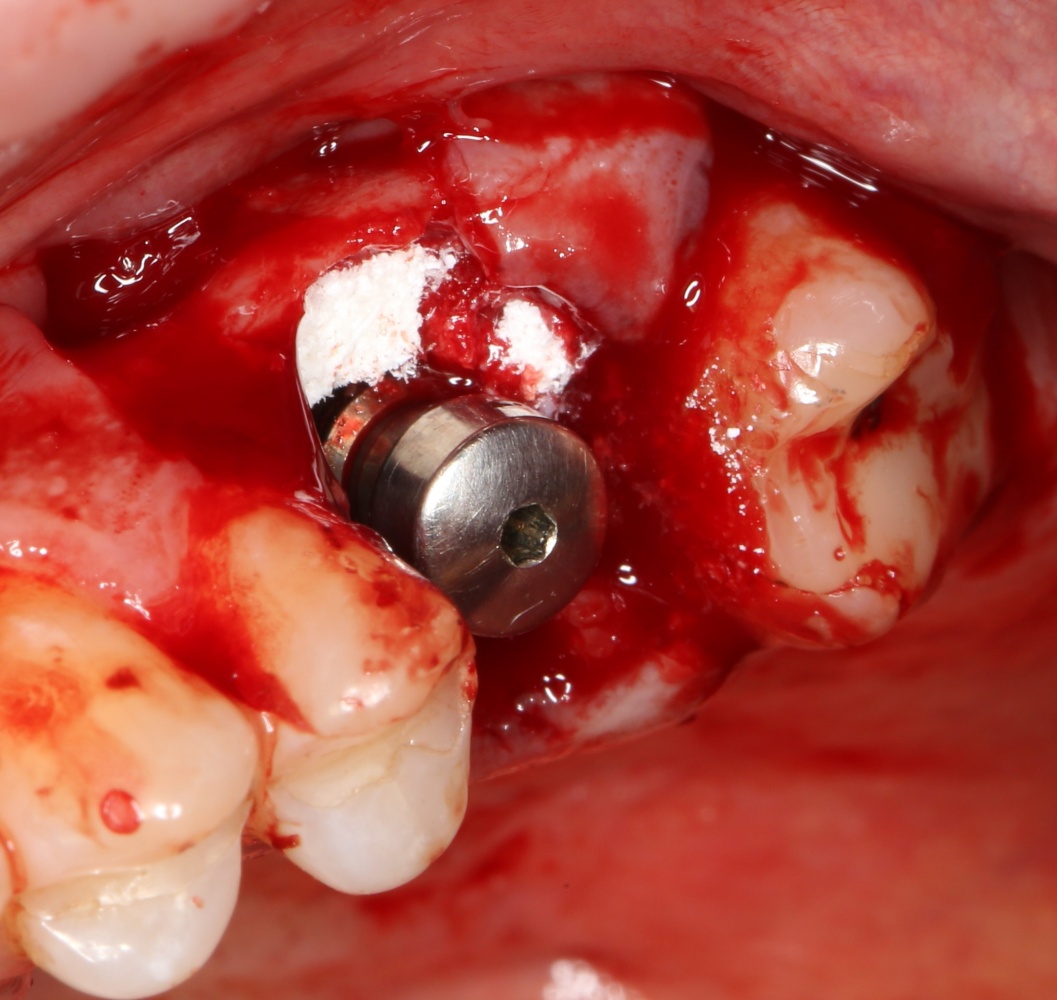

Устанавливается имплантат Astratech (Dentsply Implants):

Для аугментации также используем Bio-Oss Collagen 100 mg, нарезаем его по размеру с помощью скальпеля и позиционируем в лунках щечных корней:

На имплантат ставим формирователь, ушиваем лунку. Напомню, что любой биоматериал должен быть герметично запечатан в ране (фактор успеха III). В противном случае, от него больше вреда, чем пользы: